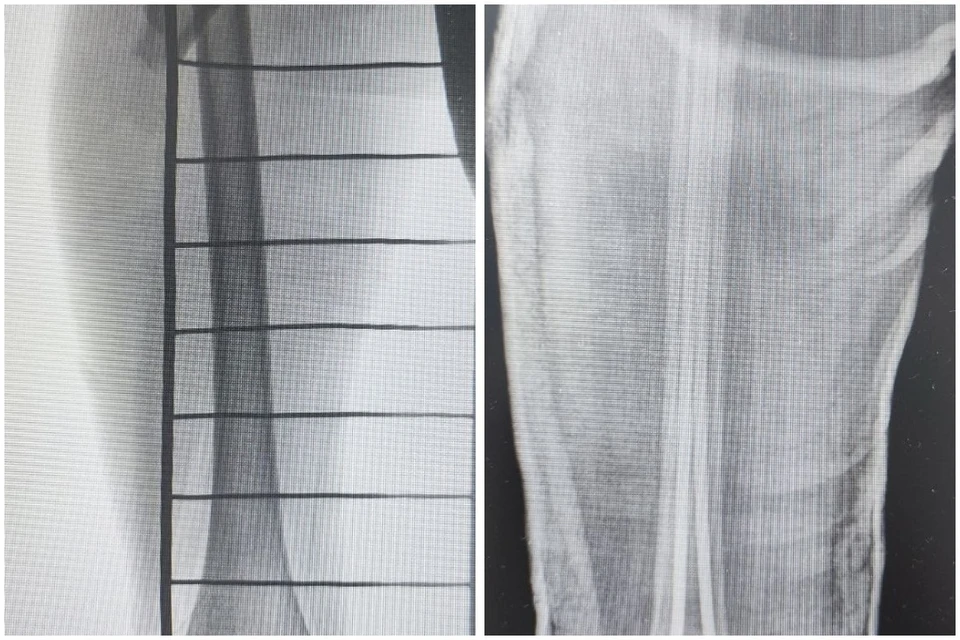

Инцидент произошел на необорудованном склоне, где отсутствовали защитные ограждения. Фото: ДРКБ Бурятии

В Бурятии ребенок получил травму во время зимних забав. В приемное отделение Детской республиканской клинической больницы обратился 7-летний мальчик, который пострадал, катаясь на тюбинге. Об этом КП-Иркутск сообщили в пресс-службе ведомства.

- Инцидент произошел на необорудованном склоне, где отсутствовали защитные ограждения. Ребенок получил травму, которую нельзя получить в оборудованном безопасном месте, - говорится в сообщении.

У мальчика закрытый перелом бедренной кости со смещением. Экстренная операция была проведена успешно. Сейчас маленький пациент получает необходимое лечение в отделении травматологии и ортопедии. На сращение перелома уйдет примерно 5-6 недель.